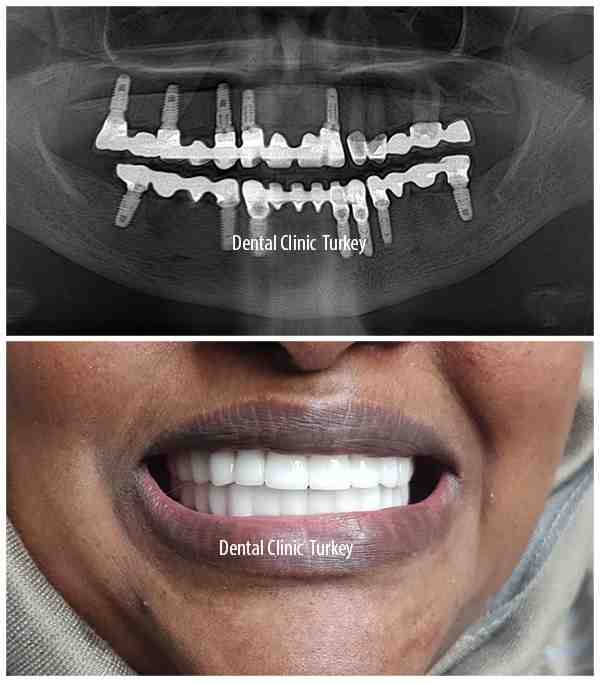

What happens if you don’t have enough bone for dental implants?

If you do not have enough bone, the bone can be rebuilt. If you don’t have enough gum, that can also be put back. This must be done before implants can be placed. The treatment is called bone augmentation and has been used successfully for years.